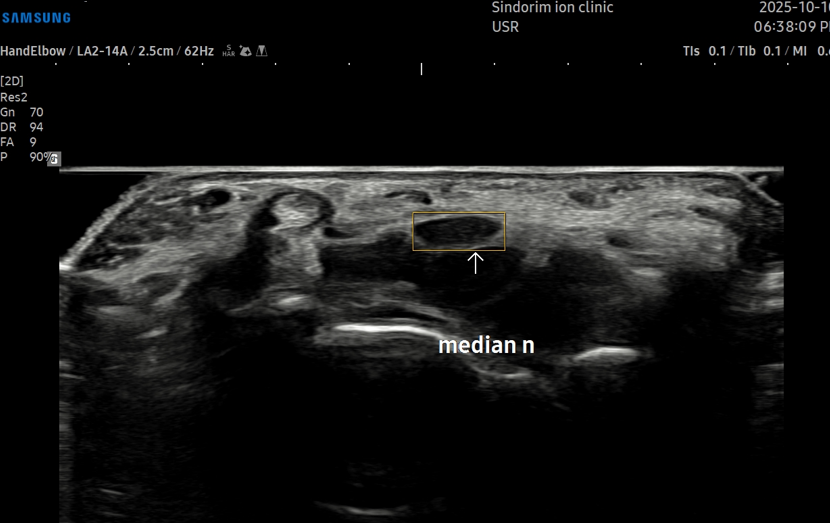

- 치료기간 : 25 . 8 .19 ~ 25 . 11 . 20

- 치료횟수 : 25 회 (사이클 치료 3 +아피톡신 10회)

치료 전

치료 후

좌측 골프엘보 : 12/2

좌측테니스엘보: 12/8

우측 골프엘보 : 12/2

우측 테니스엘보: 12/8